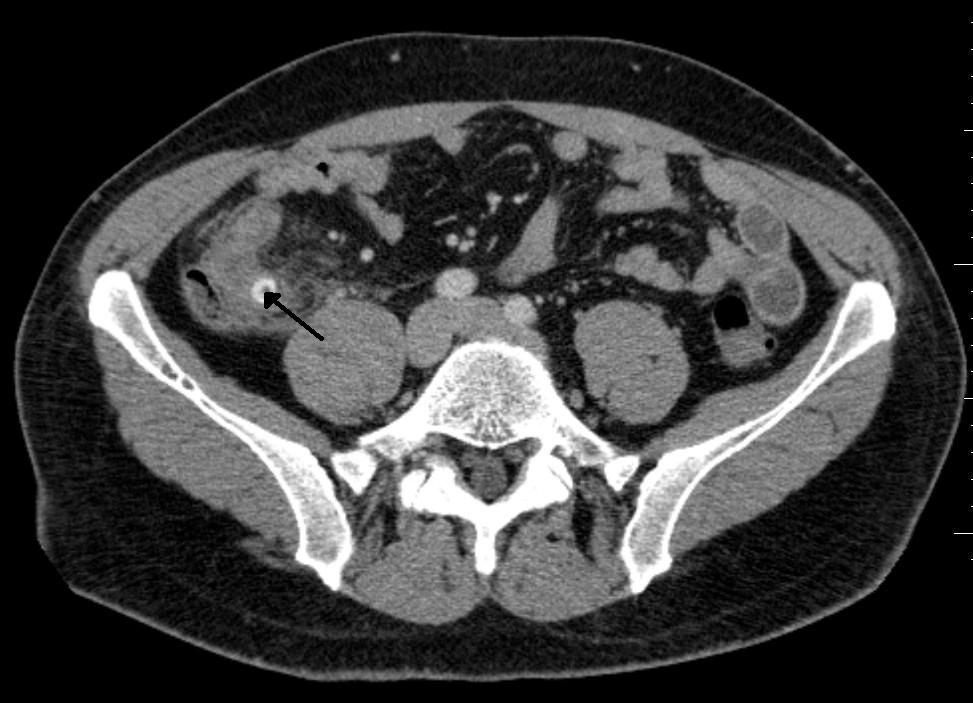

CT skeniranje: prikaže podrobne slike katerega koli dela telesa, kot so kosti, mišice, maščoba in organi.